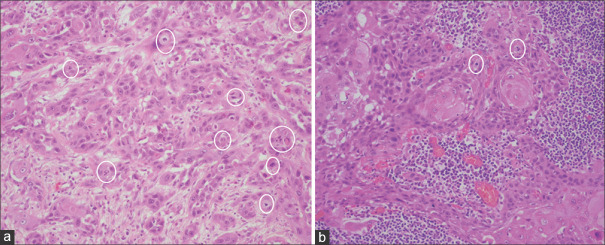

Materials and methods: A total of 510 lymph nodes from 17 cases of surgically treated OSCC were analysed, of which 40 lymph nodes were found to be positive. These 40 lymph nodes were examined histopathologically for the presence of mitotic figures in ten randomly selected fields (x400) and compared to the mitotic activity of the primary tumour by two observers independently, along with other histopathological features. LMI and PLMR were further determined for these cases.

Observations and results: The mitotic index was significantly higher in the metastatic deposits than in the primary tumour (P = 0.004). A higher percentage of abnormal mitoses was observed in metastatic lymph nodes, but no statistical significance (P = 0.27) was found when compared with primary tumour. Statistically significant correlation (P = 0.001) was observed between abnormal mitoses (%) and presence of ECS as well as size of the metastatic deposits. The LMI ratio showed a high mitotic rate in close to 80% of the cases. PLMR showed 58-60% cases with mitotically more active lymph nodes.